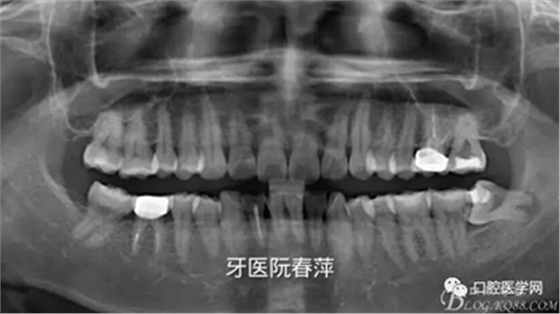

戴牙后全景片:

【X光片檢查】

后牙的修復體X光線阻射應該強于釉質,以方便日后對繼發(fā)齲的檢查。X光片還能從直觀上對修復體邊緣是否密貼,鄰面有無懸突進行進一步的檢查。

絢彩AT無飾瓷全形態(tài)氧化鋯產品體驗+全冠和嵌體微創(chuàng)修復后牙